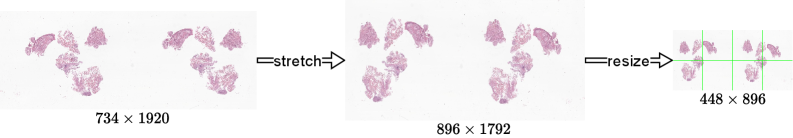

3.2 Pre-Processing

Using the OpenSlide library [9], we extracted a thumbnail from each WSI: either the auxiliary thumbnail image stored in the file or, if unavailable, the lowest pyramid level resized so that its longest side is 1,9201{,}920 px. All thumbnails were oriented so that the width exceeded the height and stretched to a common size of 896×1,792896\times 1{,}792 px. Depending on the desired resolution, the images were then resized to one of four scales (Table 2) and divided into a grid of non-overlapping 224×224224\times 224 px tiles (Figure 4). The complete workflow is illustrated in Figure 5 for the M configuration.

Refer to caption

Figure 4: Stretched slide thumbnail with tile grids overlaid. Red: L grid (4×84\times 8), green: M grid (2×42\times 4), blue: S grid (1×21\times 2).

Figure 5: Pre-processing workflow for the M configuration. The thumbnail is stretched to 896×1,792896\times 1{,}792 px, resized to 448×896448\times 896 px, and divided into a 2×42\times 4 grid of 224×224224\times 224 px tiles (green).